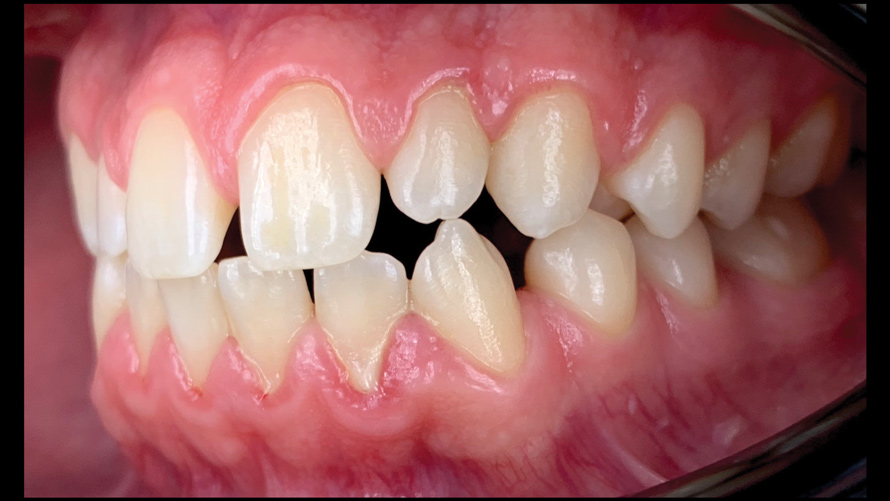

(12. and 13.) Intraoral photographs taken with a smartphone and an EALS device for orthodontic evaluation.

Figure 12

Figure 13

One of the main advantages that smartphone cameras have over DSLR cameras is that nearly everyone is already very familiar with the technology; therefore, the incorporation of these devices into everyday practice does not require learning a new and unfamiliar skill set. The task of producing a series of high-quality clinical photographs for routine examinations (Figure 8), esthetic treatment planning (Figure 9 through Figure 11), or specialty care (Figure 12 and Figure 13) can be delegated with confidence to any staff member during the patient's initial office visit and will generally require less than 5 minutes of time to complete. When a DSLR camera is used, evaluation of the intraoral images either takes place on the small viewfinder built into the camera or necessitates the physical removal of the memory card from the camera to downloaded the images onto a computer for review. An added bonus of smartphone dental photography is that the phone's screen now replaces the much smaller viewfinder of a DSLR camera and provides the clinician with the ability to view and zoom into the patient images on a 5- to 6-inch, high-definition display.